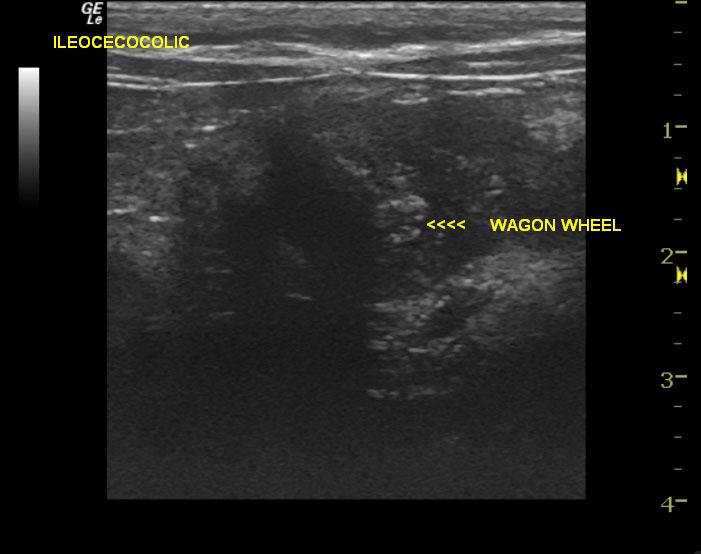

A 1-year-old male neutered Ragdoll cat was with history of chronic eye problems presented for decreased appetite and loose stools for 3 days. Physical exam found patient pyrexic at 104.4 degrees fahrenheit. Suspected enlarged lymph nodes were found on abdominal palpation. Subcutaneous fluids were administered, and patient was discharged with appetite stimulants. Blood chemistry and CBC were within normal limits. FELV/FIV and FIP tests were all negative. Toxoplasma results were normal.